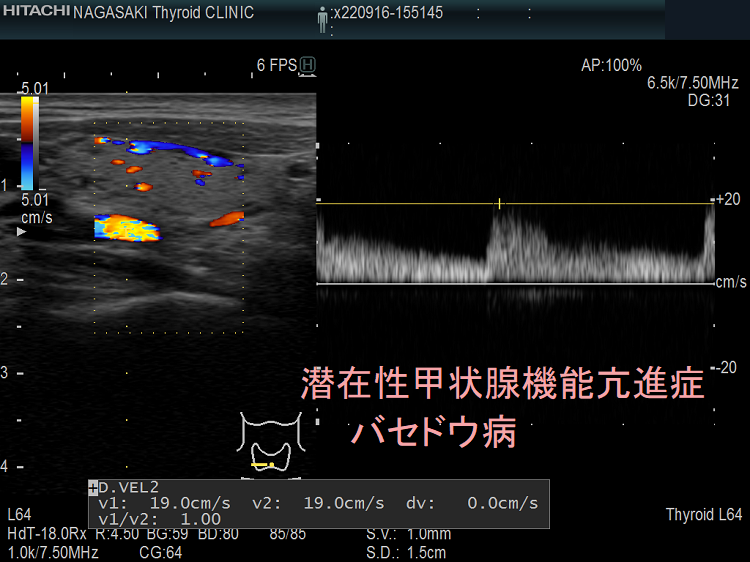

血液検査に加えて、医師は身体検査を行って、甲状腺の肥大や手の震えなど、甲状腺機能不全の兆候がないかどうかを確認します。また、甲状腺の構造を評価するために、甲状腺超音波検査などの画像検査を依頼することもあります。

原因がバセドウ病または中毒性多結節性甲状腺腫である場合、治療の成功率は高く、良好な結果が得られます。ただし、他の病気と同様、見通しは個人と治療に対する反応によって異なります。